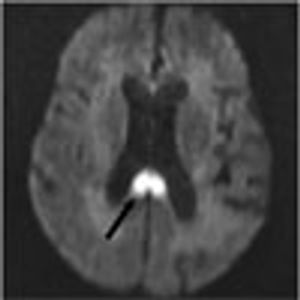

A 68-year-old woman was hospitalized because of confusion and agitation of sudden onset. Her history included dementia and multiple infarcts of both cerebellar hemispheres, bilateral basal ganglia, bilateral parietal lobes, and the right occipital lobe.